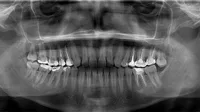

UD5 Radiología Bucodental

Quina va ser la primera radiografia de la història?

Una mà amb una polsera

Una mà amb un anell de matrimoni